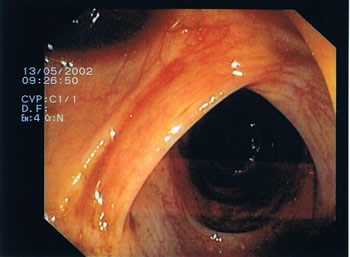

Endoskopische Bilder. Das Darmlumen innerhalb der einzelnen Darmabschnitte kann eher rundlich, leicht eingeengt oder dreieckförmig aussehen, entsprechend des anatomischen Aufbaus (s. Abb.1-4). Grundsätzlich gibt es verschiedene Arten von Polypen mit unterschiedlichen Konfigurationen und von verschiedener Größe. Kugelig(Abb.6) mit schmaler Verbindung zur Darmwand, hügelig mit breiter Basis, muschelförmig, die sich häufig an eine Querfalte anschmiegen, gestielte Polypen, die über einen Stiel mit der Darmwand verwachsen sind und sessile Polypen (Abb.5), die breitbasig auf der Darmwand aufsitzen. Der Übergang zum Dünndarm (Ileocaecal-Klappe) kann des Öfteren ein polypöses Aussehen vortäuschen (Abb.4).